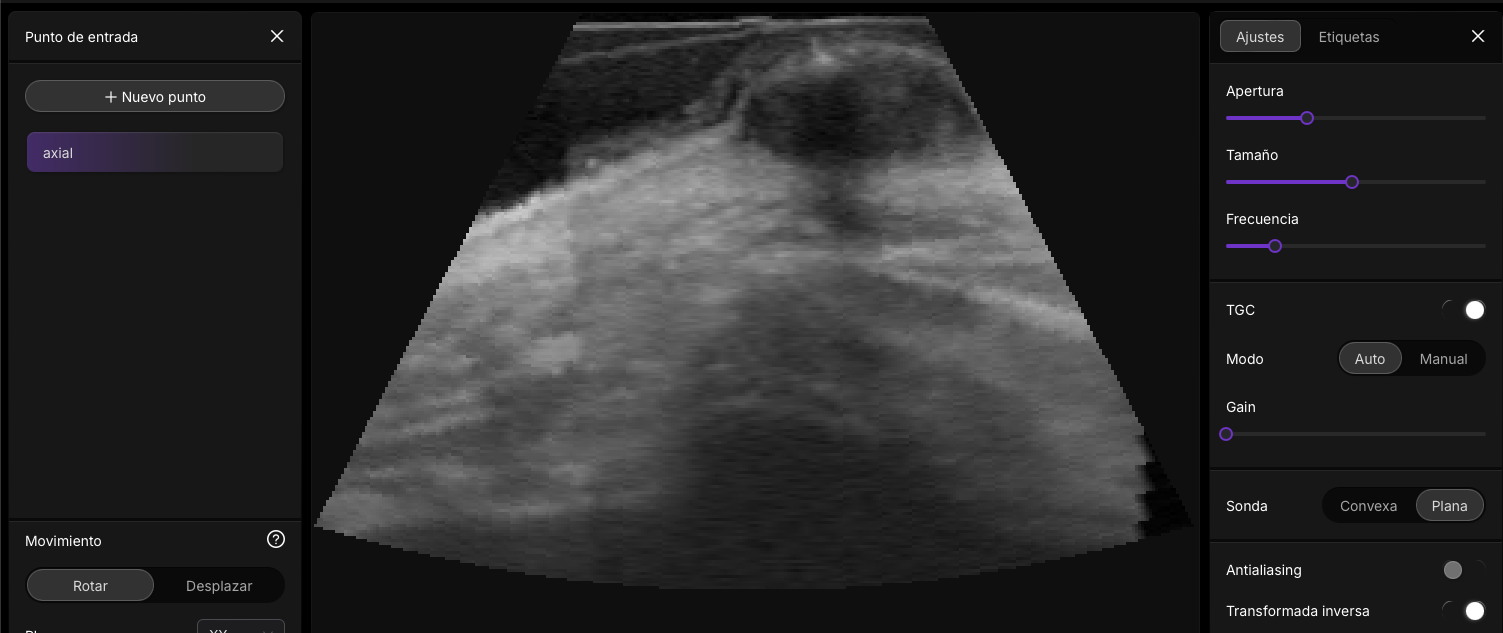

👉📟 Ir a Imagineus®.

Esta intefaz de usuario, la podras encotnar en el modulo del curso II: Parametros nivel avanzado ( pronto)